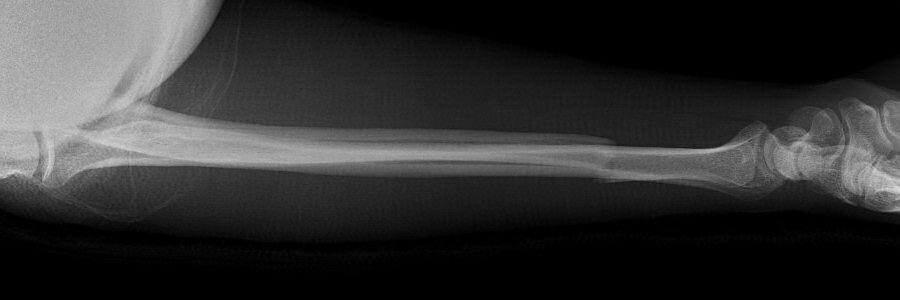

Fraktur tvärfraktur distala tredjedelen med < 50 % felställning och < 10° vinkelfelställning (nightstick fracture)

Kalkgips (plastgips glider för lätt ner) eller ortos på underarm med fri armbåge och fri handled. Återbesök med röntgenkontroll efter 1 och 8 veckor, avgipsning efter 2 veckor (!) och därefter rörelseträning till smärtgräns. [4, 5]

Nightstickfraktur